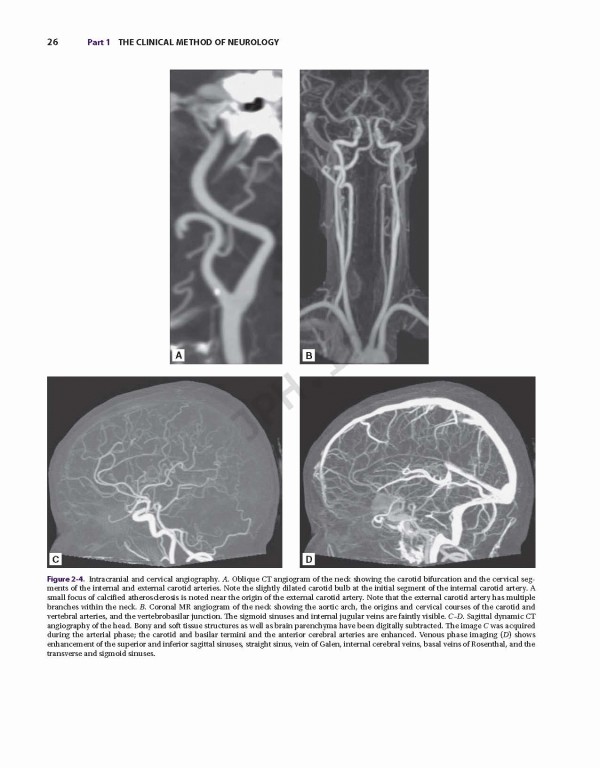

کتاب Adams and Victor's Principles of Neurology 11th Edition 2019، اصول نورولوژی آدامز و ویکتور یک کتاب مشهور که پزشکان را به درک عمیق از جنبه‌های اصلی بیماری عصبی، از جمله داده‌های بالینی و جدید علمی راهنمایی می کند. این متن دقیق و تجدید نظر شده و به روز شده‌، همچنان یک شاهکار در زمینه خود است و خواندنی ترین مرجع موجود. در صفحات آن، شما می توانید توصیفات انضباطی از داده‌های بالینی و توضیحات روشنی از روند بیماری‌های زمینه‌ای را پیدا کنید.

Adams and Victor’s Principles of Neurology is truly the classic text in its discipline --- a celebrated volume that guides clinicians to an in-depth understanding of the key aspects of neurologic disease, including both clinical and new scientific data. This meticulously revised and updated text remains the masterwork in its field, and the most readable reference available. Within its pages, you will find a disciplined presentation of clinical data and lucid descriptions of underlying disease processes.

•A rich, full-color presentation that includes many high-quality illustrations